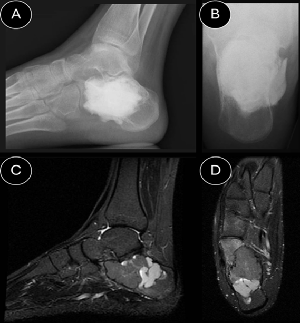

Limb Salvage Surgery with Customized Titanium Prosthesis for Management of Calcaneus Osteosarcoma

Gabriel de Jesus Narváez, Fernando Cabrera, Jhon Alexander Muñoz, Dario Sebastian Arcos